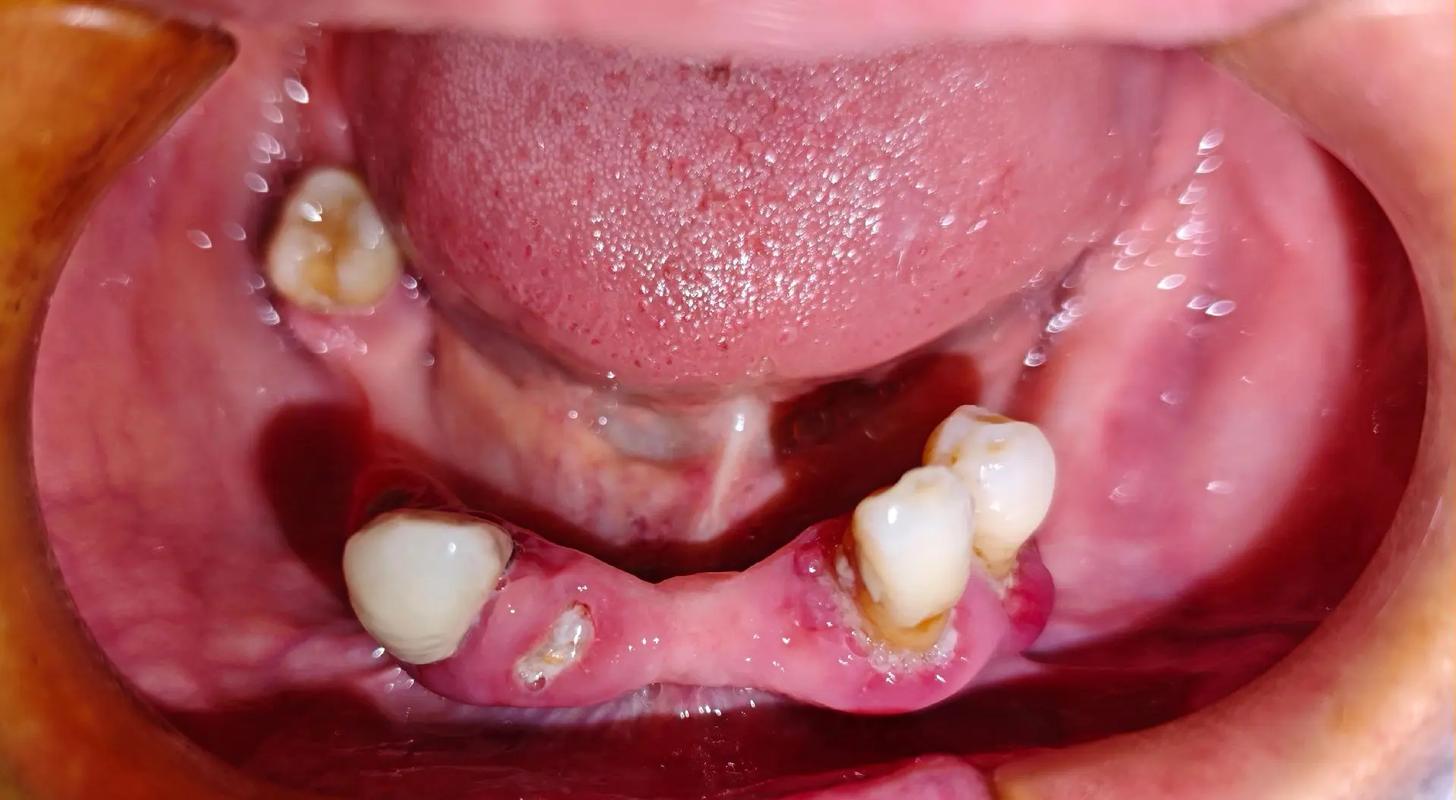

种植牙流程通常分为术前检查、方案设计、手术植入、戴冠修复及术后维护五个阶段,术前需进行口腔全景片、血常规等检查,评估骨量、全身健康状况;方案设计阶段,医生会结合患者咬合习惯、美学需求制定个性化方案;手术植入在局部麻醉下进行,一般30分钟至1小时完成;骨整合期(3-6个月)后,安装基台和牙冠,最终完成修复,整个过程需患者与医生密切配合,术后定期复查以确保种植体长期稳定。